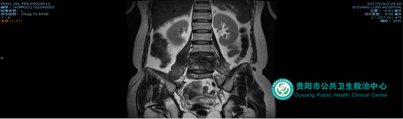

病例2:病人為胸腰椎結(jié)核年輕患者,胸背痛、后凸畸形明顯,胸9--10椎體結(jié)核,后凸角35度,經(jīng)過后路矯形、前路支撐,基本恢復(fù)脊柱生理曲線。

術(shù)前

術(shù)后